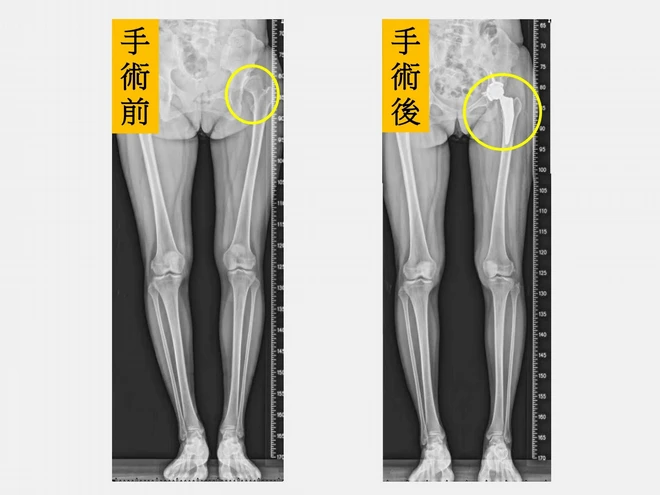

髖關節發育不良」(Developmental Dysplasia of the Hip,DDH)是指股骨頭與髖臼在成長發育過程中未能形成良好穩定的結構,造成髖關節從不穩定到脫位不等的情況。長期下來關節受力不均,會加速軟骨磨損與退化,進而引發早期退化性髖關節炎,常見症狀包括疼痛、僵硬、跛行及長短腳等,嚴重影響生活品質。

仁愛長庚合作聯盟醫院骨科部長黃贊文指出,因髖關節發育不良導致的髖關節炎多好發於40~55歲,且以女性居多。若在兒童時期就診斷出來,可進行髖關節截骨矯正手術;若成年後才發現,可進行截骨矯正手術延緩人工關節置換的時程;但若病情已進展到末期,則建議直接安排人工髖關節置換手術。

「微創正前開髖關節置換手術」術後疼痛減輕,恢復速度較快,行走步態也更穩定。(圖片來源:仁愛長庚合醫院)